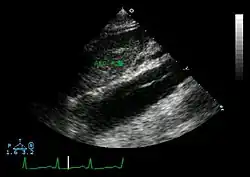

Ultrasound

The transesophageal echocardiogram (TEE) is a good test in the diagnosis of aortic dissection, with a sensitivity up to 98% and a specificity up to 97%. It has become the preferred imaging modality for suspected aortic dissection. It is a relatively noninvasive test, requiring the individual to swallow the echocardiography probe. It is especially good in the evaluation of AI in the setting of ascending aortic dissection and to determine whether the ostia (origins) of the coronary arteries are involved. While many institutions give sedation during transesophageal echocardiography for added patient comfort, it can be performed in cooperative individuals without the use of sedation. Disadvantages of TEE include the inability to visualize the distal ascending aorta (the beginning of the aortic arch), and the descending abdominal aorta that lies below the stomach. A TEE may be technically difficult to perform in individuals with esophageal strictures or varices.

-

Aortic dissection with an intramural hematoma as seen on TEE

Type A aortic dissection[36]

Dissection of both the thoracic and abdominal aorta[37]